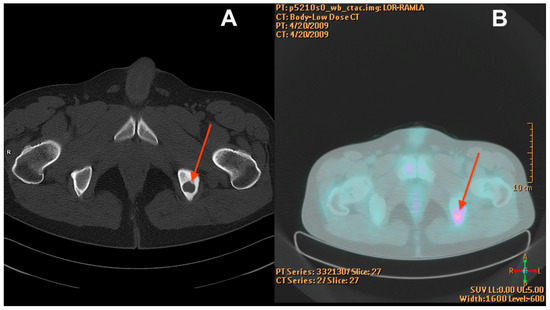

Before the diagnosis of EHE, the patient underwent biopsy procedures three times in 2010, 2012, and 2013 due to a focal lesion of the ischium on the left side (Figure 1). During each procedure, the material was collected for histological examination.

Figure 1. CT scan from 2009 (A) showing a well-demarcated osteolytic lesion in the left ischium (red arrow). The mean density of the tumour in the pre-contrast scan was 87 Hounsfield units (HU) and showed moderate enhancement in the subsequent phases reaching 112 HU in the venous phase. PET-CT from 2009 (B) with increased radiotracer uptake at the tumour location (red arrow).